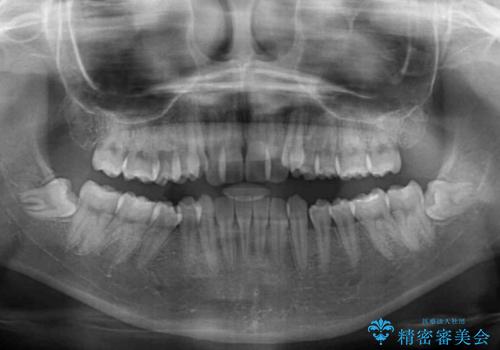

- 前歯のデコボコと八重歯を気にして来院された患者様です。

目立たない装置を希望されたので、上顎が裏側装置のハーフリンガルを選択し、左右上顎小臼歯1本ずつを抜歯して、矯正治療を行うこととしました。